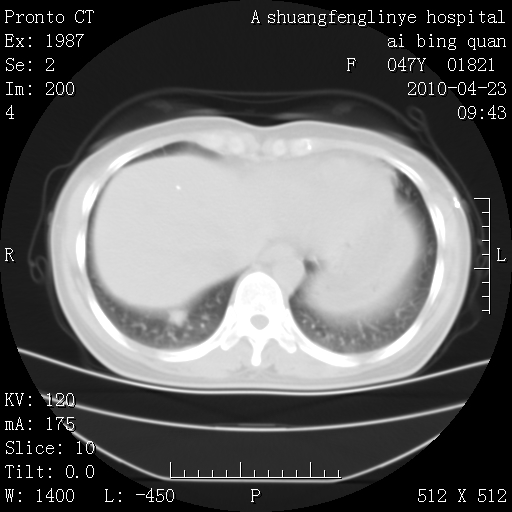

标题: CT25944:胸痛、气短、前几日高烧!肺Ca?请会诊! [打印本页]

标题: CT25944:胸痛、气短、前几日高烧!肺Ca?请会诊!

双肺多发结节,考虑转移瘤,肺癌肺转移不除外

周围型肺癌并肺转移

左侧乳腺低密度灶

双肺多发结节,部分密度较高,最大结节边缘光滑。临床有“胸痛、气短、前几日高烧”病史。首选考虑:右肺感染性病变!建议积极消炎后复查!